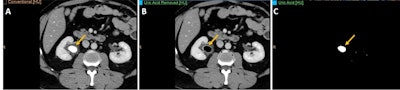

A 43-year-old man with right renal colic. (A) Conventional image shows a large stone in the right renal pelvis of indeterminate composition. (B, C) Spectral images confirm the presence of a uric acid stone. This is clinically relevant as uric acid calculi can be treated medically (urinary alkalinization), whereas other calculi (calcium, etc.) may require interventional procedures (stone removal or external shock wave lithotripsy). All figures courtesy of Dr. Ana Villanueva Campos et al and presented at RSNA 2023.